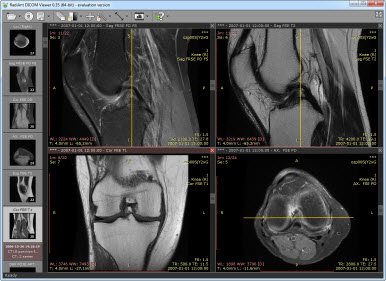

DICOM(Digital Imaging and Communications in Medicine)은 표준 의료영상/기록 포맷이다:

- 주로 병원 내 'PACS(Picture, Archive, Communications)' 시스템에 의해 처리된다.

- 현재 거의 대부분의 의료영상기록이 DICOM 포맷으로 저장된다.

- X-ray, CT, MRI 등 다양한 의료 영상 데이터를 포함한다.

Figure 1.23 DICOM 뷰어를 통한 의료 영상 데이터 관리